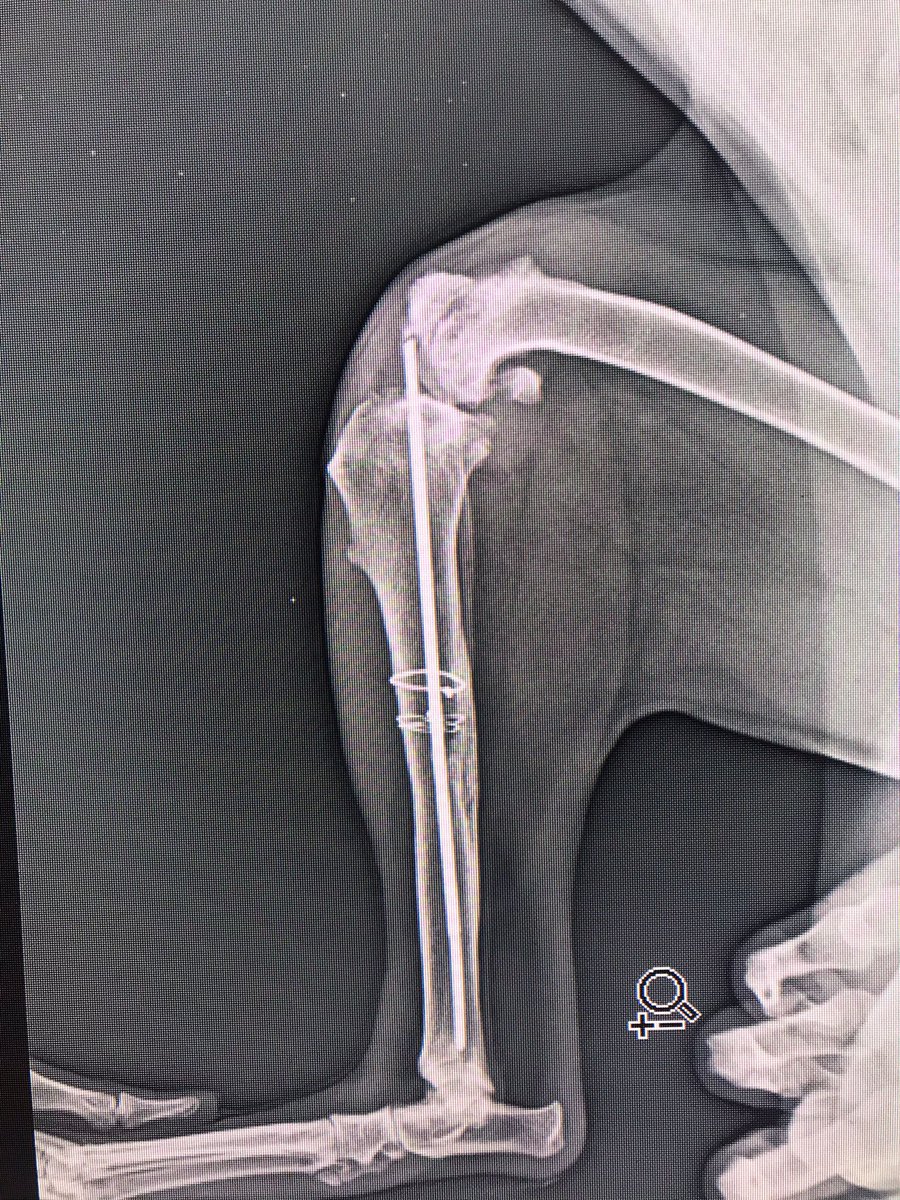

Yanlış yapılan operasyonun röntgeni şu şekilde. Ordaki pin dize baskı yapa yapa orayı eritmiş, kullanılamaz hale getirmiş artık. Bu yüzden o kısım alındı ve yerine protez takıldı. Operasyon ve protez masrafı için 100 lira destek olabilecek 55 gönüllü arıyorum.